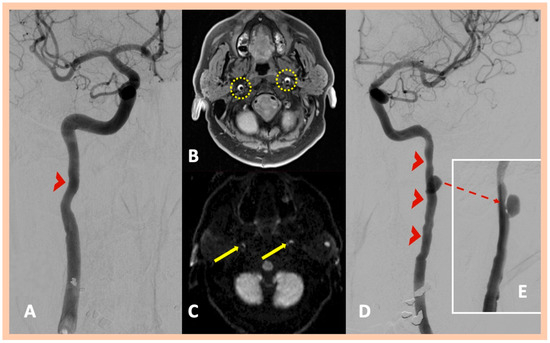

| Pat. #1 | Acute right MCA infarction | Right internal carotid “flame-like” occlusion (≈1 cm above the bifurcation) | Intramural hematoma along the distal cervical and proximal petrous artery segments and mural hematoma in the intraforaminal segment of the right (V2) vertebral artery | Confirmed MRA findings | Symptomatic right ICA and asymptomatic right V2 dissections | 2 | No |